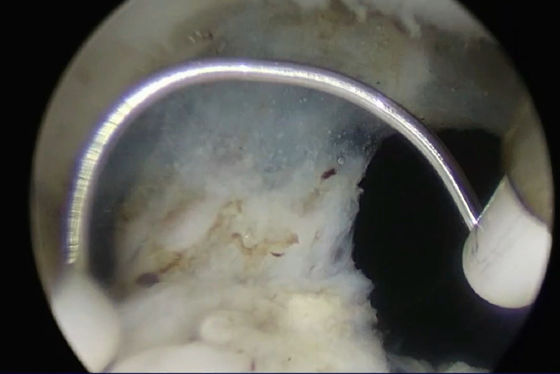

تأثير الجراحة الفعليهـذا هـذا

قبل قطع بعد قطع